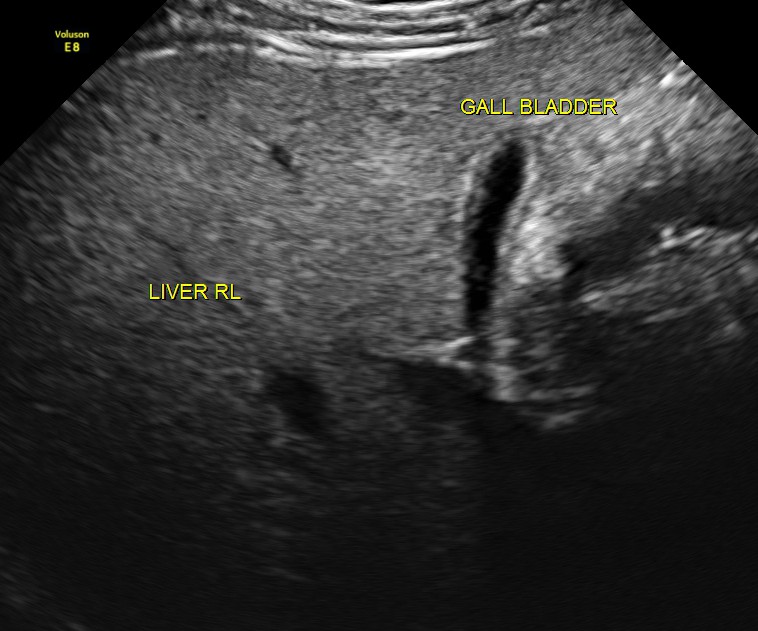

The following pictures were obtained.

An echogenic nodule with vascularity is seen.

The scan was otherwise normal.